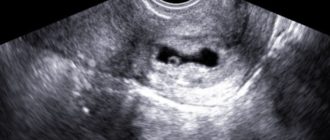

Деформировано плодное яйцо

Деформированное плодное яйцо на ранних сроках беременности 23.11.2017 Плод при беременности Деформация плодного яйца